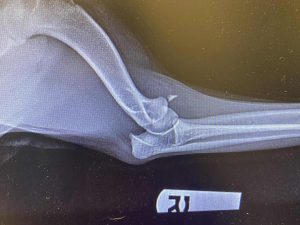

Shortly after the first public post about the Blue Heeler, she was struck by a car. Her jaw was broken, and her leg was dislocated. Thankfully, she was rushed to Priority Pet Care in West Plains, where Dr. Wes Gunter and his team immediately began emergency care.

The team acted quickly, performing emergency surgery to repair her jaw and leg. She pulled through.